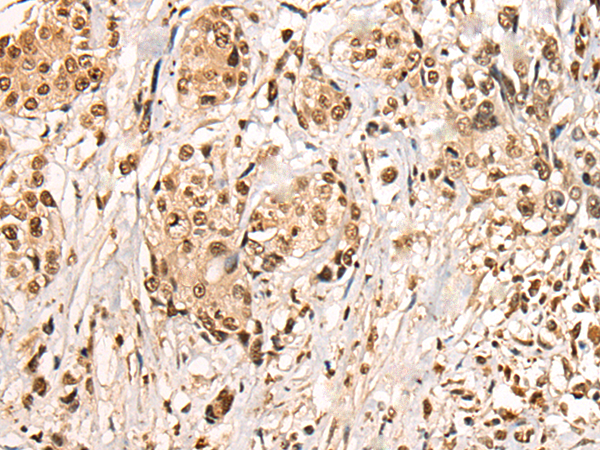

IHC positive control: |

Human prostate cancer |

IHC Recommend dilution: |

20-100 |